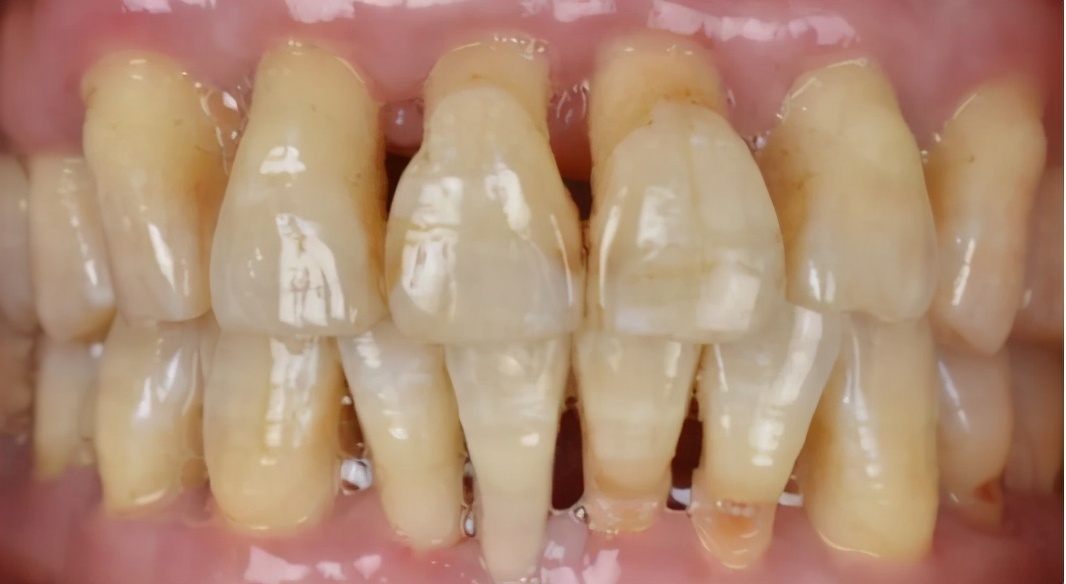

(牙周病患者的口内情况,牙龈牙槽骨萎缩,前牙松动外展)

小结:牙齿不齐,首选创伤最小,效果最持久的牙齿矫正,不适合牙齿矫正的患者,再考虑其他方式修复。